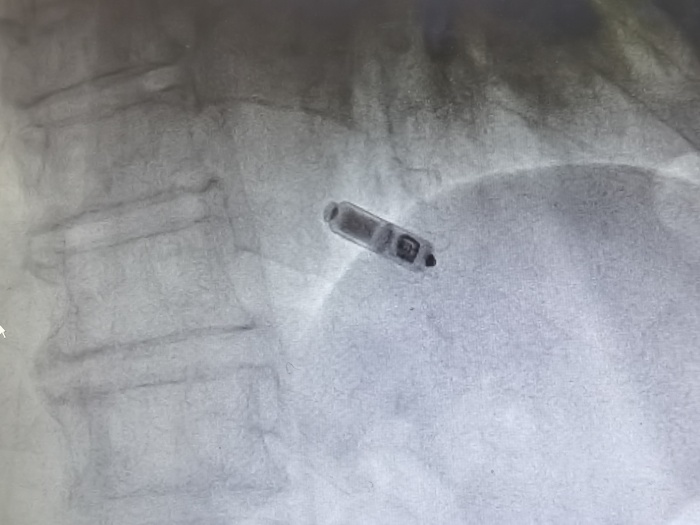

(圖示為植入心臟內(nèi)的Micra? AV無導(dǎo)線起搏器)

金奇志主任醫(yī)師告知:“無導(dǎo)線起搏器是集脈沖發(fā)生器與電極導(dǎo)線于一體的新型起搏器,無需靜脈植入心內(nèi)膜導(dǎo)線,通過以“微縮膠囊”的形式植入患者的心腔內(nèi)。無導(dǎo)線起搏器植入簡(jiǎn)單、美觀,無囊袋及導(dǎo)線植入相關(guān)并發(fā)癥,不影響肢體活動(dòng),可以明顯提高患者的自信心和治療體驗(yàn),安全性與穩(wěn)定性也比較好?!?